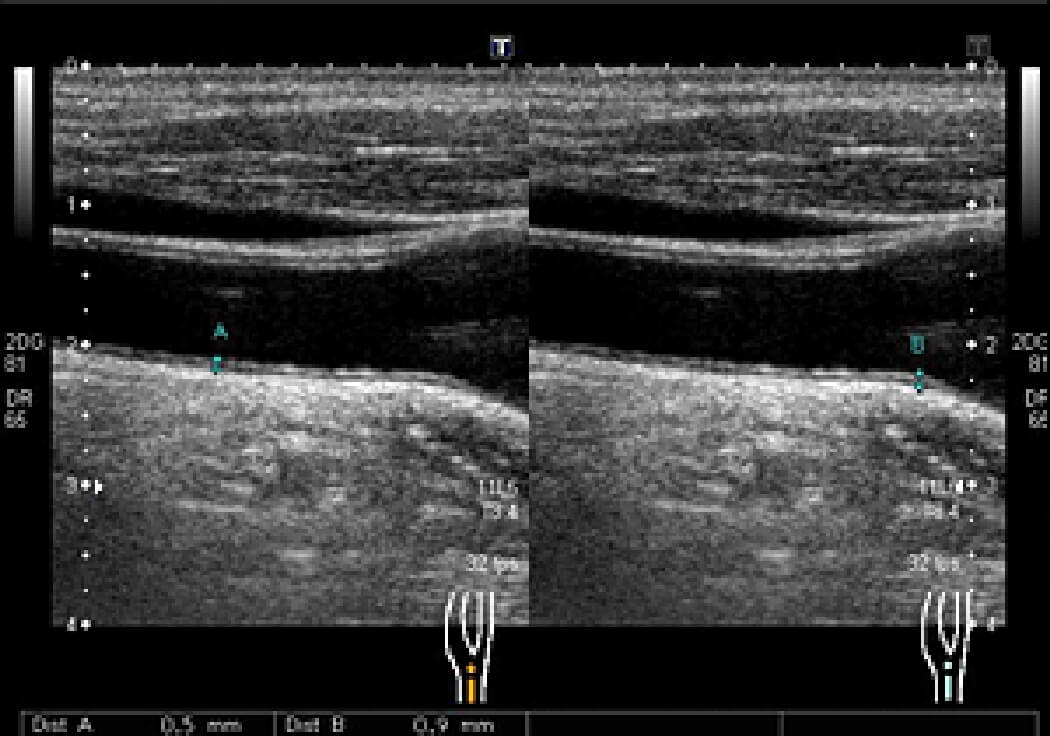

正常な頚動脈

頚動脈プラークの例